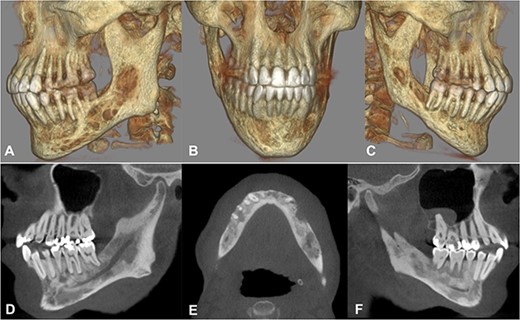

In 2020, a 99 m Technetium scintigraphy was performed to rule out disseminated osteomyelitis. The scintigraphy showed no other foci of enhancement but the mandible with increased inflammatory activity in the anterior portion of the jaw (Fig. 1). Magnetic resonance imaging (MRI) was performed to analyze the localization and extent of the disease. In Fig. 2, a high inflammatory activity, resembled by a strong local enhancement in the T2 weighting, was seen, reaching from the right condyle to the left. Cone beam computed tomography (CBCT) confirmed a widespread patchy radiolucency extending to both left and right mandibular condyles (Fig. 3). Hard tissue biopsies were taken to rule out malignancy due to the disease’s extensive destruction and chronic course. Blood assays were also requested.

Cone beam computed tomography. A–C) Three-dimensional reconstruction showing the severe destruction of the mandible. D–F) Sagittal and axial sections showing coexisting patchy radiolucent areas within the mandible reaching up to the condyle on both sides.